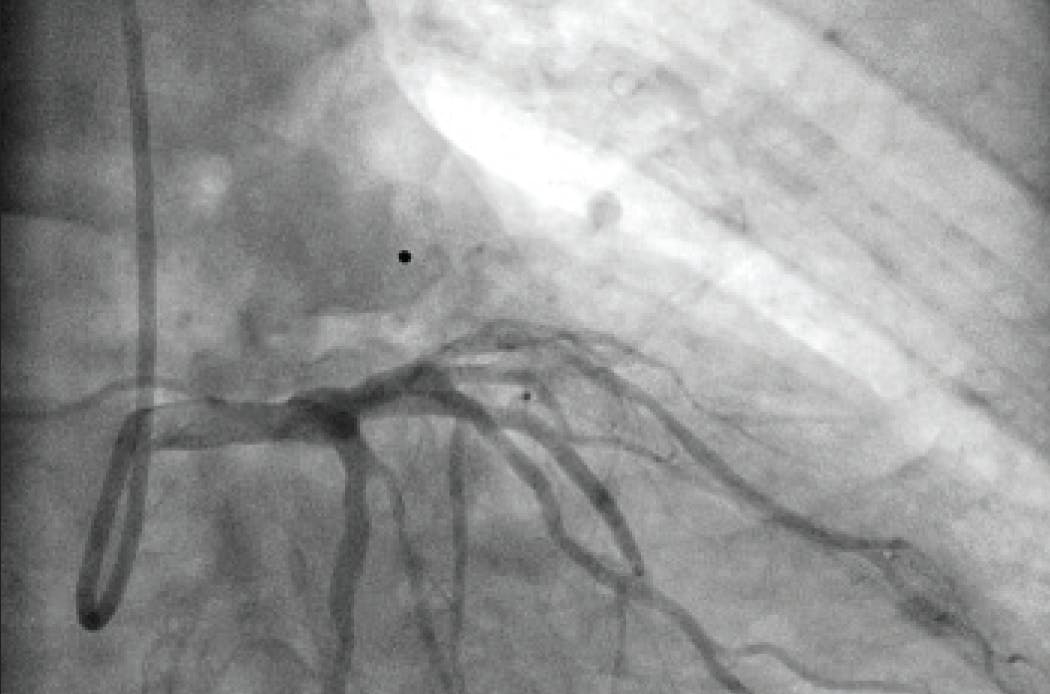

After achieving wire access, the Lightning Flash 2.0 was inserted. While in “Gallop Mode,” the saddle clot burden and subsequently the left and right main PAs were aspirated. Once the algorithm returned to “Sampling Mode,” aspiration was turned off and angiograms were obtained to assess the progress. After 5 minutes of aspiration, reperfusion of the main PAs and distal branches was achieved (Figure 3, Figure 4, and Figure 5), with improvement in the patient’s vital signs and no device-related complications.

Figure 3. Postthrombectomy angiogram of the left lobe.

Figure 4. Postthrombectomy angiogram of the right lobe.